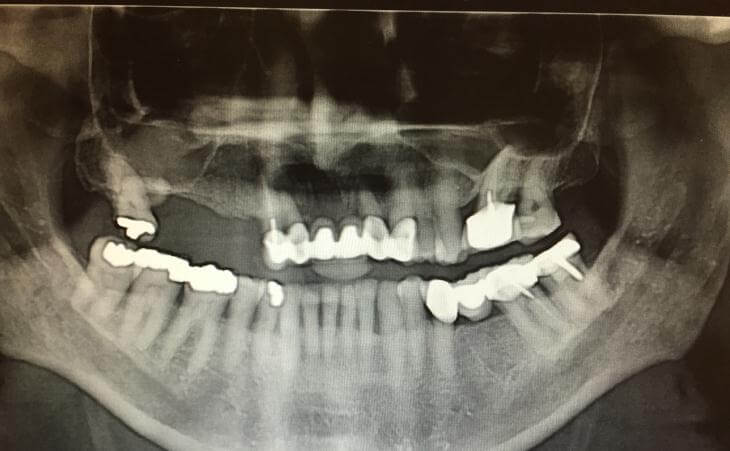

40 year old male with fractured upper left molar. Tooth was extracted, bone was regenerated. Then a surgical guide was made for proper implant angulation and placement. Internal sinus elevation was accomplished in order to avoid a Sinus Lift. An implant was placed and restored.

59 year old male who wore an upper full denture for over 20 years wanted to convert his situation to a non removable implant supported restoration. Using guided implant surgery and planning, nSequence, I was able to plan the precise position of his implants and place them using a surgical guide. The restorative dentist then placed his teeth attached to his newly placed implants the same day - a total makeover!!

This 46 year old male had non usable loose lower teeth that could not be saved. he did not want to wear a denture during the healing process. I planned to remove all his lower teeth and using guided implant surgery place implant and deliver permanent teeth the same day. The entire case tooth 3 hours and he left the office with a new set of non removable teeth attached to newly placed 7 dental implants. The transformation was remarkable

46 year old male has been missing his upper teeth for years and wore a denture. He had severe dental phobia . Using Advanced guided surgical technique, I was able to plan his entire surgery virtually, create a surgical guide (template) and place his implants in the most ideal positrons. Virtual planning held to shorted surgical time and thus improves technique and recovery.

Patient presents with all upper teeth in state of decay, loose, not able to make a new bridge. This case was planned with a prosthodontics colleague, to extract all upper teeth, place dental implants and immediately, same day, place temporary bridge on the implants so patient can leave with teeth same day of surgery and wear these temporary teeth for approximately 6 months until the implants are healed and final teeth can me made. The implants are placed using a computer guide made ahead of the surgery to assure implants and planned teeth are in the exact planned positions. Dr. Stein and Dr. Koslovsky are among the only oral surgeons with the skill to do this type of complex implant placement.